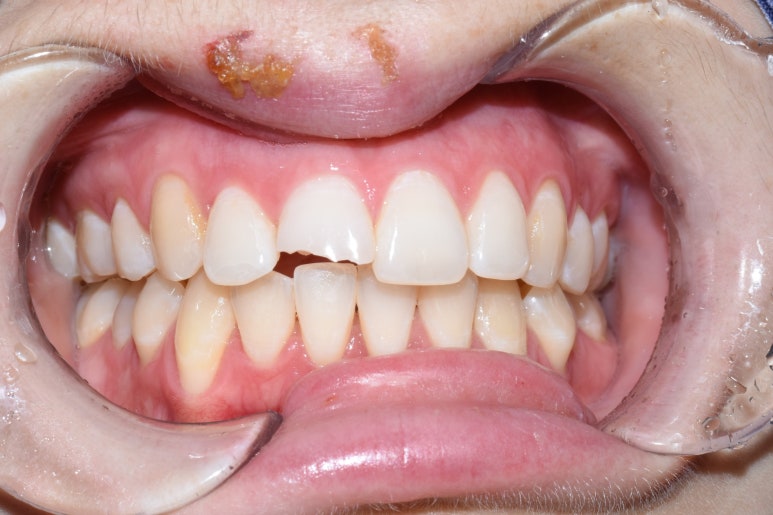

회사생활을 위해 임시로 급하게 앞니를 떼운 모습 (왼쪽) -> 깨진 앞니 크라운을 완성한 상태

넘어져서 앞니가 많이 깨져서 오셨는데

치료를 물론 받으셔야 하지만 회사에서 점심시간에 잠깐 나오신 거라

사회생활을 하기 위해 임시로 앞니를 떼워드린 후

치료를 진행하여 앞니 크라운이 완성되었습니다.

깨진 치아 크라운을 하시는 김에

삐뚤었던 앞니를 교정하는 효과와 치아 색을 더 밝게 하는 효과를 넣어드려서

2개만 치료했지만

나머지 치아들도 더 전반적으로 깔끔해 보이는 효과가 생겼습니다.